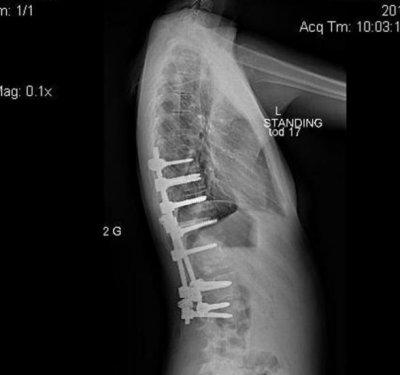

Manken Zoe Blenkinsop dünyaya skolyoz rahatsızlığıyla geldi. Sırtındaki omuru S şeklinde eğri olan genç kız, uzun süre ayağa kalkmakta bile zorlandı.Her seferinde büyük acılar çeken genç kızın sırtında bir yumru oluştu.

2011 yılında Zoe nihayet ameliyata alındı

Sırtına metal çubuklar yerleştirildikten sonra eğri olan omuru buna bağlandı.

Ameliyat tam 7 saat sürdü.